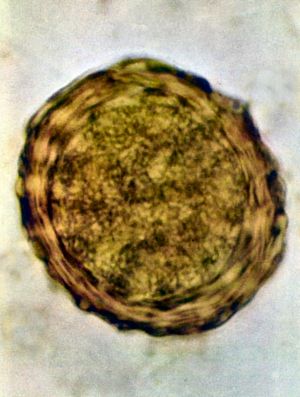

회충의 교미는 숙주의 몸 안에서 행해지며, 수정은 수란관 안에서 이루어진다. 수정란은 물결 모양의 난막으로 둘러싸여 있다. 이 막은 점착성이 있어서 다른 물체에 부착하기 쉽고, 건조를 막아주는 역할도 한다. 수정란은 1주일 후쯤 제1기 유생이 되어 난막 속에서 움직이는데, 유생의 몸은 약간 검고 표면에 수많은 작은 알갱이가 있다. 난막 안에서 탈피하여 제2기 유생이 되면 감염 능력을 얻게 되지만, 환경 상태가 나쁠 때에는 수개월에서 수년 간 난막 안에서 지낼 수도 있다. 숙주의 창자 안에서는 제2기 유생이 부화하여 자유생활을 하며, 탈피를 되풀이하여 제3, 제4, 제5기를 거치는 동안 생식기가 완성되고 암수를 구별할 수 있게 된다.

수정된 알은 타원형 또는 둥근 모양이며 길이는 45μm에서 75μm, 폭은 35μm에서 50μm이며 두꺼운 바깥 껍질을 가지고 있다. 수정되지 않은 알은 길이가 88μm에서 94μm, 폭은 44μm이다.[9]